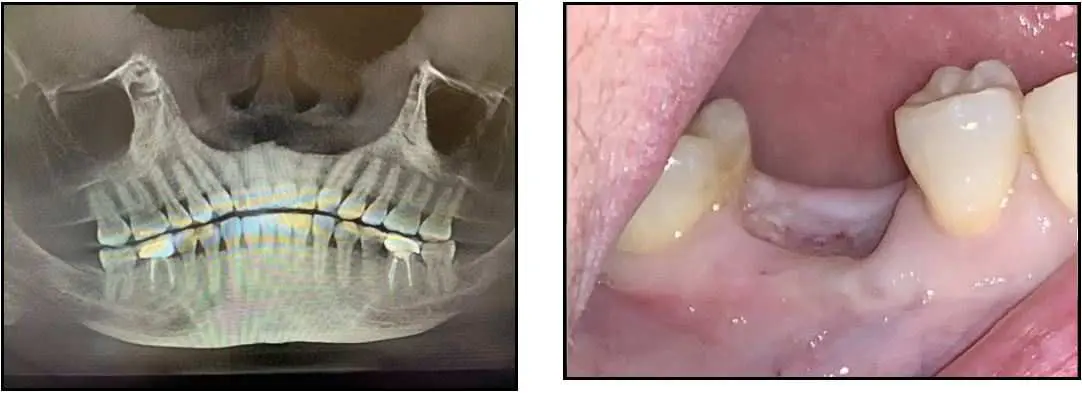

ZERAMEX® XT Case Report

This case documents a delayed placement of 2 ZERAMEX XT 5.5x10mm implants followed by immediate fixture level impressions and placement of healing caps. The patient traveled 2.5 hours to my office 4 weeks prior for removal of #19 and #30 with diagnosis of non-restorable and failed root canals. The teeth were extracted and grafted with platelet rich fibrin.

Patient arrived the day of implant surgery and modified osteotomies were performed in the delayed sites with no elevation of flaps. The implants were placed with ease achieving primary stability of 45Ncm. Fixture level impressions were taken the day of surgery and healing caps placed. The patient returned in 3.5 months for delivery of final crowns.